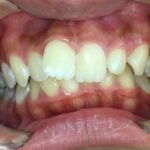

ご相談内容

「前歯のガタガタが気になる」とご相談いただきました。

カウンセリング・診断結果

拝見したところ、歯並びが全体的にガタガタしている「叢生(そうせい)」で、噛み合わせも悪くなっていました。

歯が前後に重なり合って生えている部分は歯ブラシが届きにくいため、虫歯や歯周病のリスクも高まっており、将来的に歯の寿命が短くなる可能性がありました。